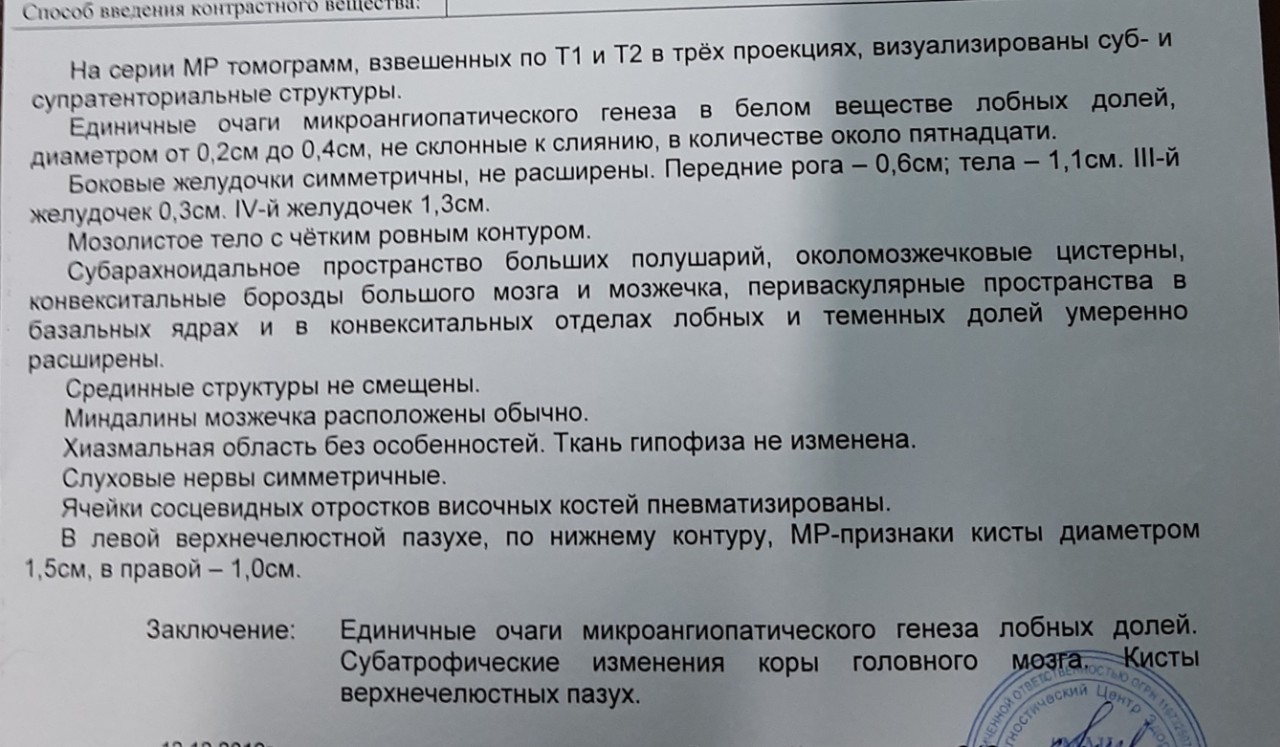

Медицинская диагностика: КТ и МРТ головного мозга

Раздел: Пульс времени